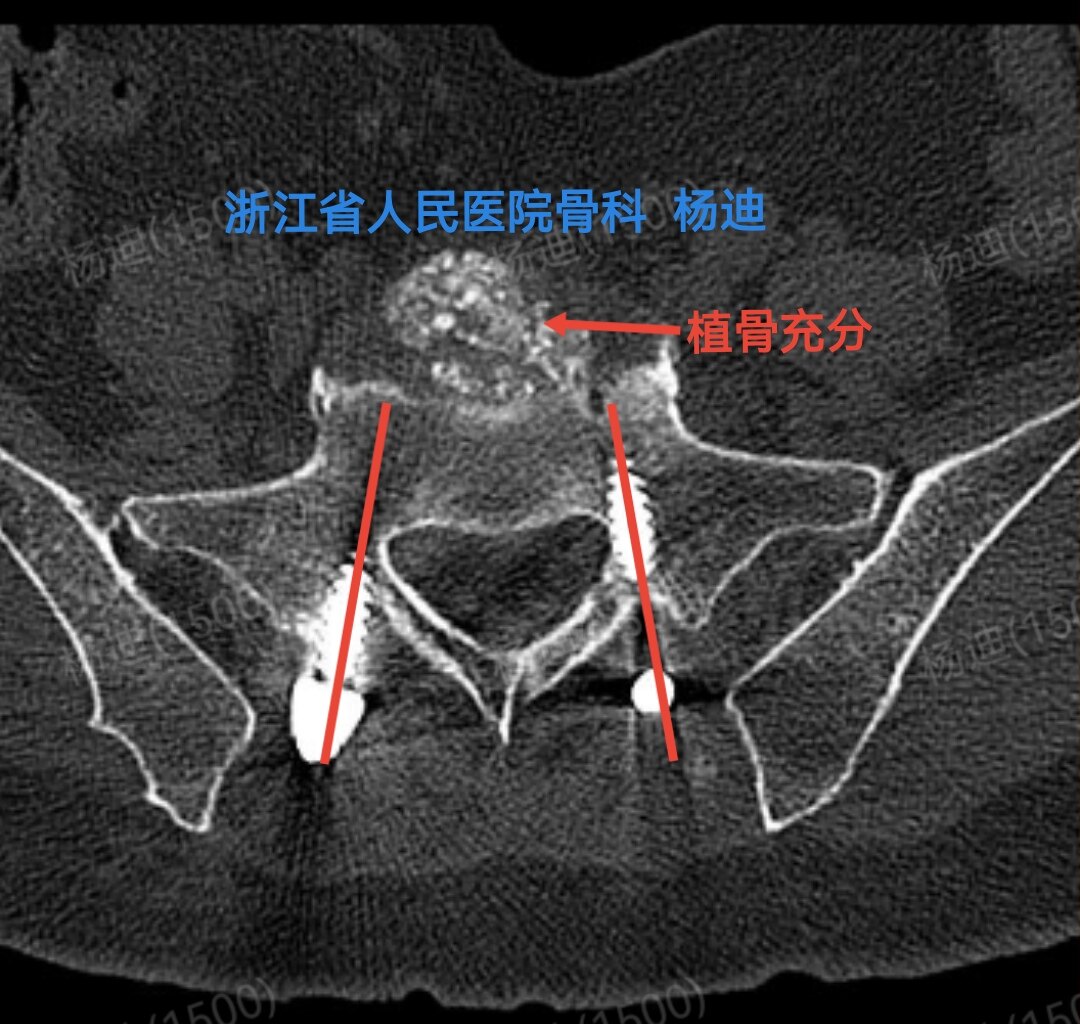

图为术后腰椎CT:骶1椎体双侧螺钉位置及长度满意(红色直线),腰5/骶1间隙植骨充分(红色箭头)。